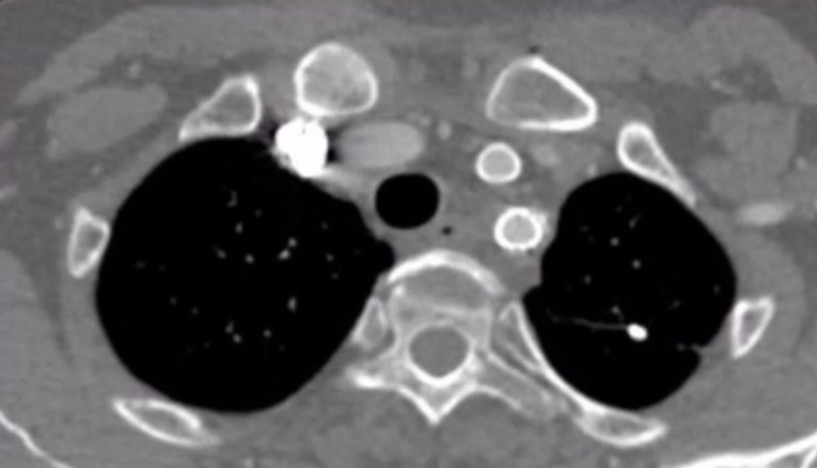

术后恢复情况

患者术后无神经系统定位体征,这意味着手术未对神经系统造成损伤,神经功能保持正常。术后五天复查CTA,可见假性动脉瘤瘤腔内已经完全血栓化,颈总动脉和锁骨下动脉分支血流通畅。出院前复查,LCCA与LSA分支形态良好,血流通畅,无狭窄,主动脉支架封闭效果好,无内漏,治疗效果令人满意。患者身体恢复良好,手术达到了预期治疗目标。

术后5天CTA